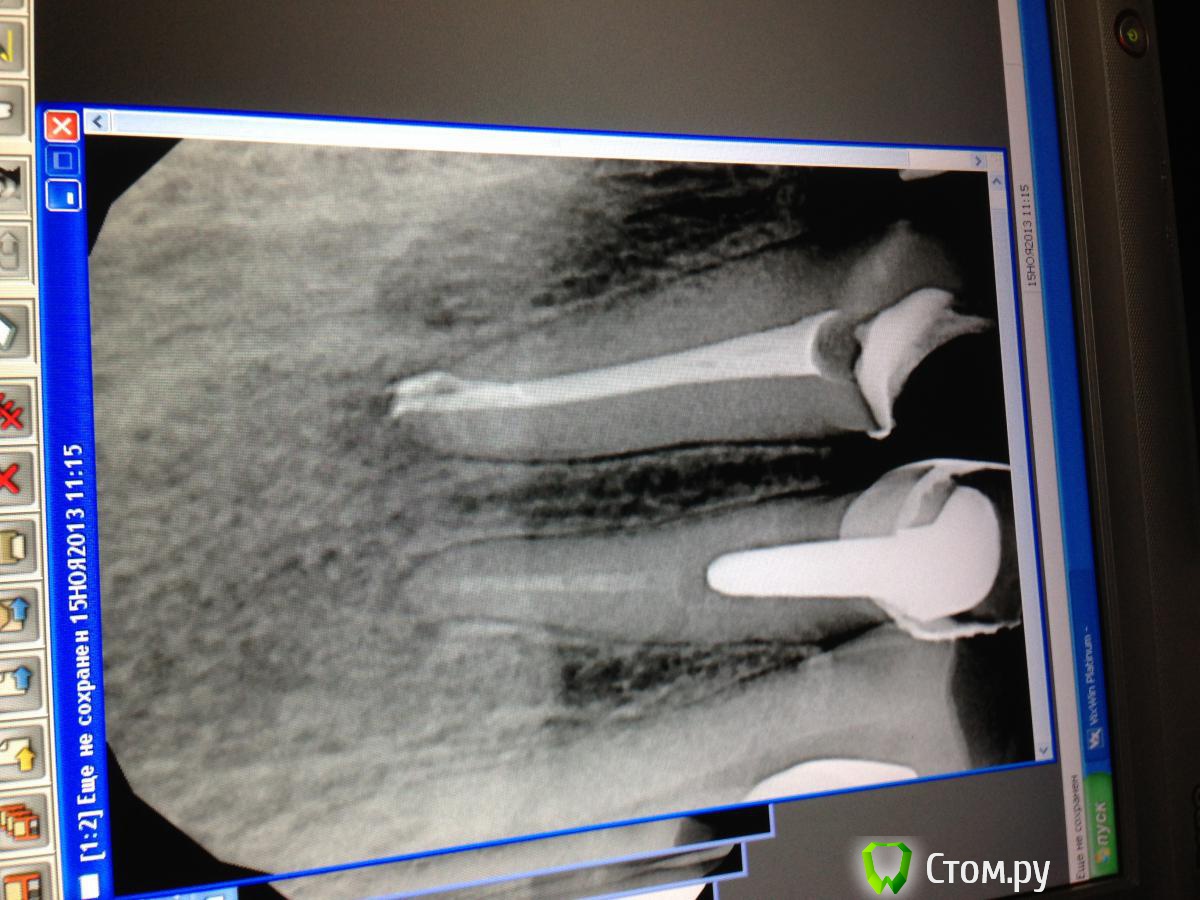

SSTi Опубликовано 4 мая, 2014 Автор Поделиться Опубликовано 4 мая, 2014 11.12.21.22. Пришел молодой человек со снимками. ( их не фоткал. Выложу как придет ) на них- ужасно запломбированные центральные резцы. 11 и 12 с резорбциями и апик очагами, 21 и 22 тоже с сюрпризами. На каждом- металлокерамика. Причем очень достойная. В 11,12 и 22 были вкв. Достал. Итак. 12. Пробился сквозь цемент( на который была зафиксирована вкладка). По снимку видел, что изгиб латерально. Сделал снимок с файлом.... В апик трети корня на медиальной поверхности или старое перфо, или резорбция. Для перфо слишком уж обширно. Помылись. Кальций. 11. Вкладку обпилил, уз добил. В канале не было ничего, кроме цемента. Запломбировал по АЛ, на 0.5 мм отступив,сделал снимок. Резил переделать. Перепломбировал не отступая, все равно на снимке как недолет. Может там резорбция и убыль корня под углом и я на снимке вижу апикально одну стенку корня( вестибулярную или небную). ??21. Еще больше впечатлений. Вкладки не было. С мыслями, что здесь все будет легче , создаю доступ, а там .... Одинокий серебряный штифт и черная пасточка. Достаю. Мою. Пакую. 22. Ничего особенного. Достал вкладку. Канал пустой. Запаковал. С 12 наверно будем расставаться. Не могу попасть в канал апикально. Все время выходит медиально в эту резорбцию-перфо. Да и феррула там нет никакого. Вопрос еще есть. Что с 11? Оставлять так? Ссылка на комментарий